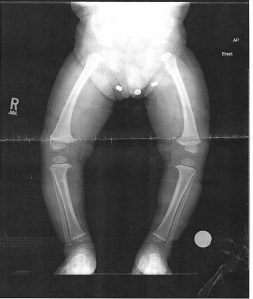

April 8, 2015. Malachi’s legs before braces. Notice buckle of his knees.

April/May 2015